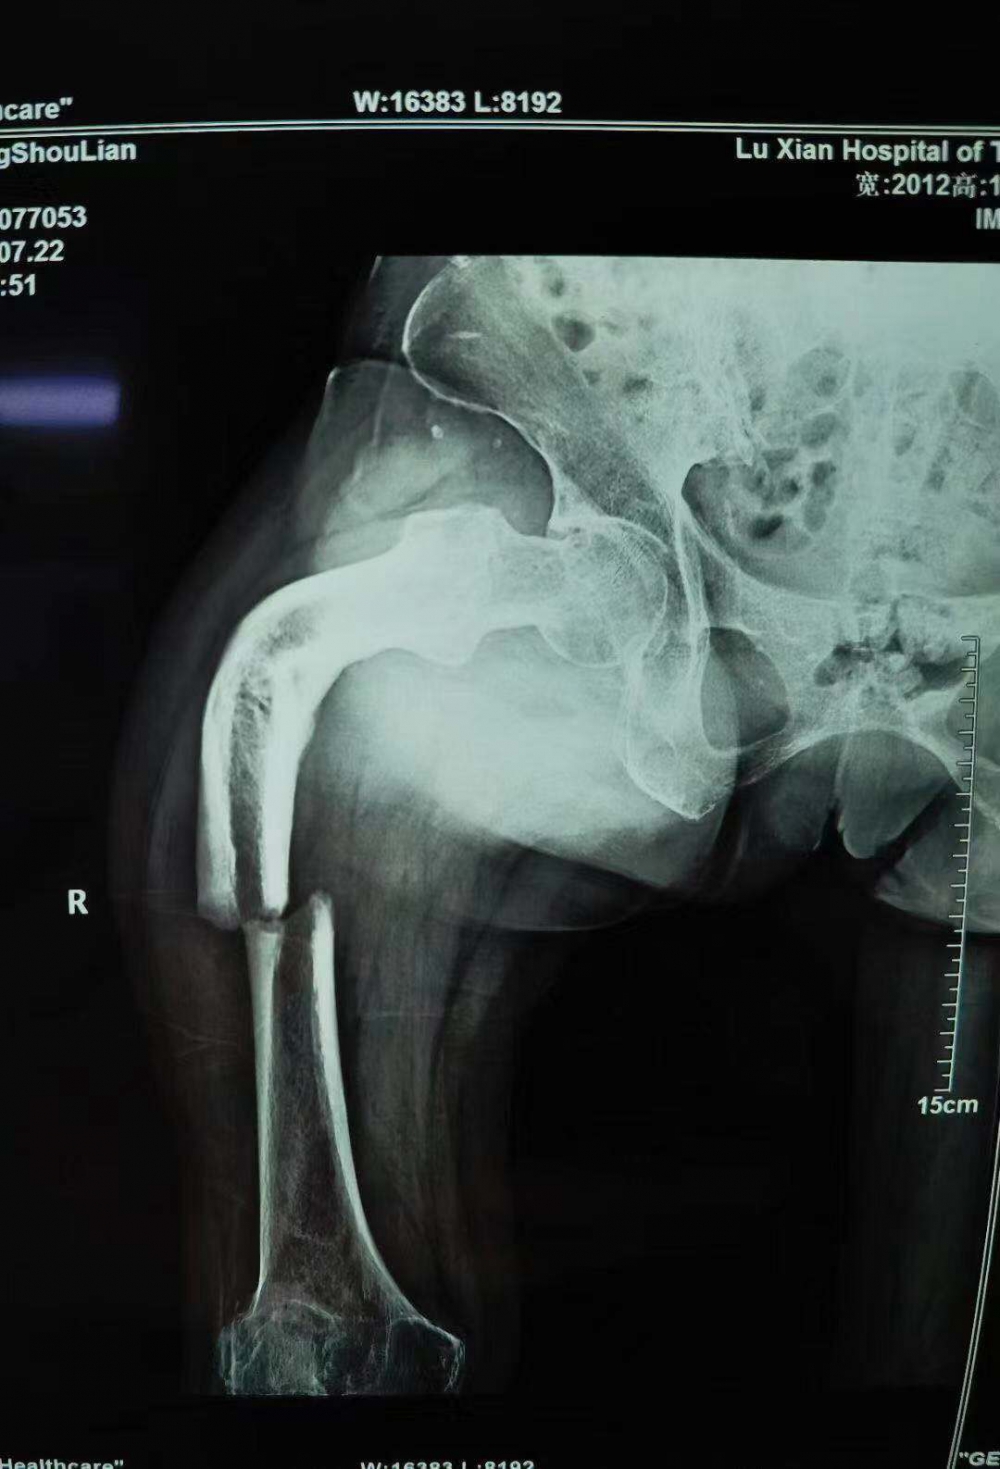

66歲的張守蓮怎么也想不到,她最近在家門口壩子走路時不小心摔斷了腿,卻因禍得福,把自己三年來跛足的腿一并醫(yī)治正常了。 (8月9日,張守蓮康復鍛煉走路) 樹要發(fā)枝,腿也會發(fā)“新芽”? 張女士家住瀘縣云錦鎮(zhèn),常年在家務農。近日,她在家門口壩子走路時,不小心把大腿摔斷,家人隨即打了120,送到當?shù)鼗鶎?..